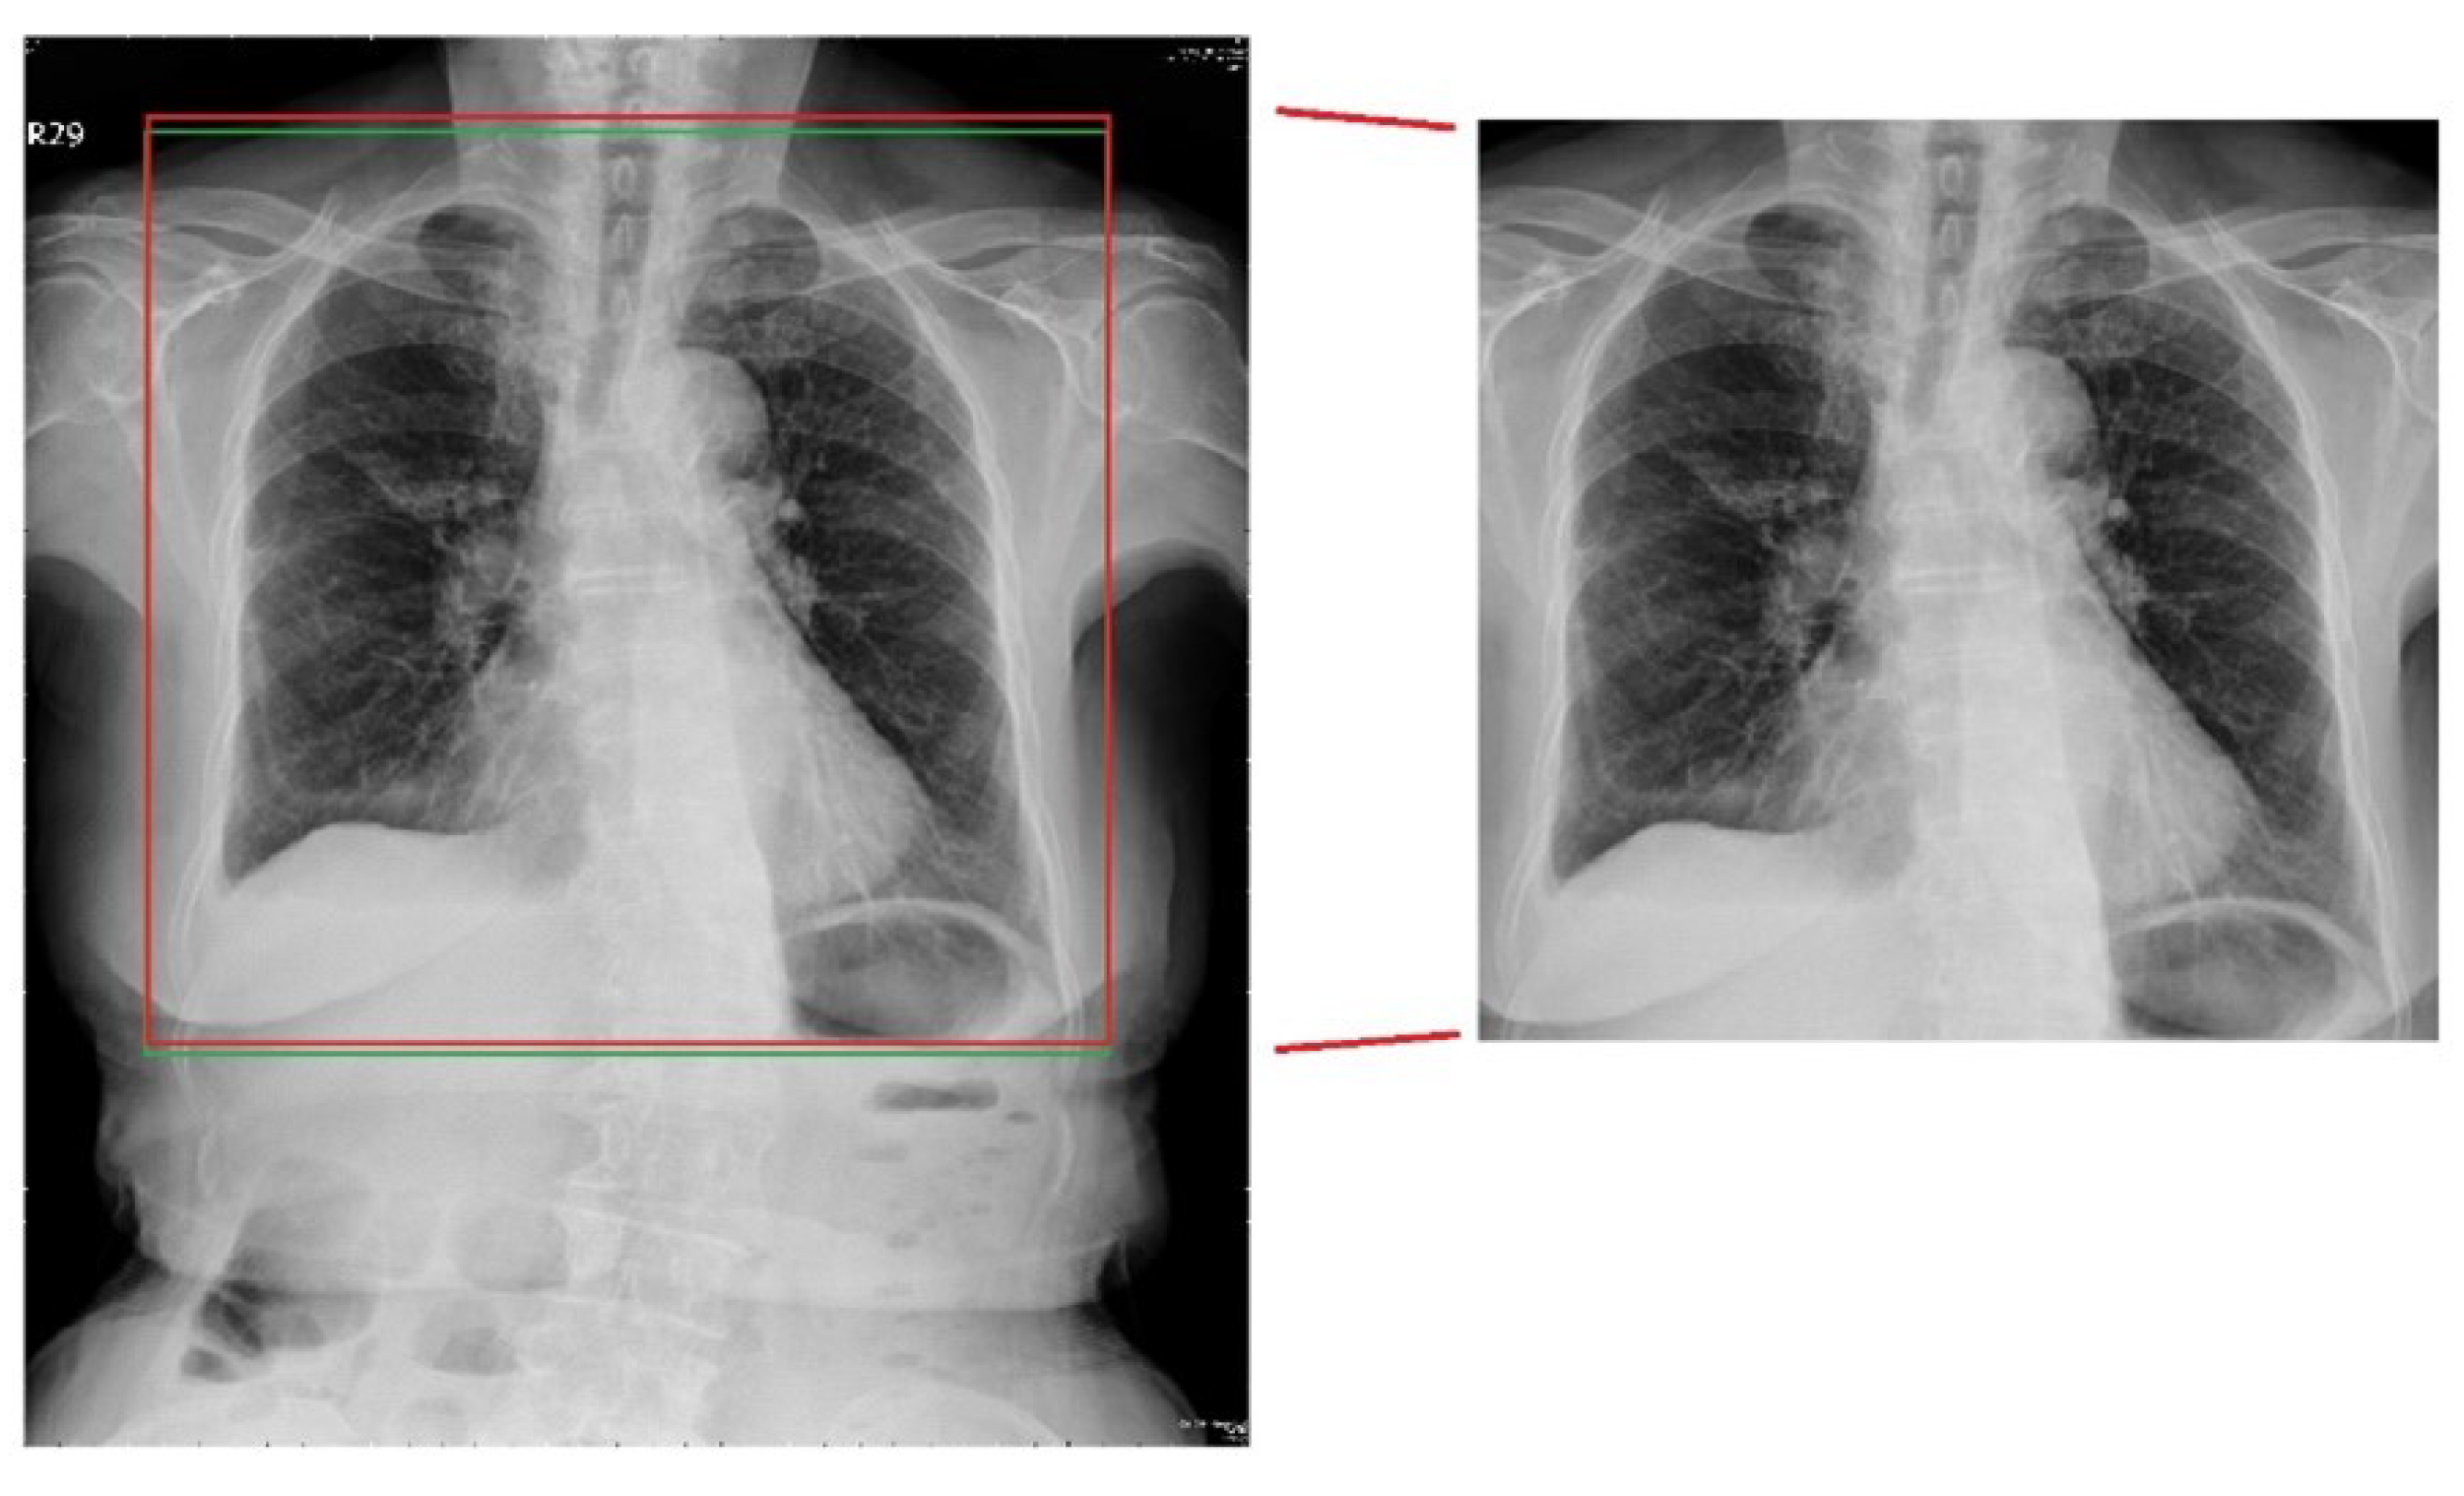

The results of the traditional lung-area segmentation method at each stage of the operations are depicted in Figure 8. In the last lung boundary identification stage, the red frame indicates the detected area, while the green frame shows the ground truth area for comparison. As can be seen, while the traditional method successfully identified the general lung area, it failed to capture the finer details at the lung boundary, resulting in slight misalignment with the ground truth area.

Figure 8.

Traditional segmentation result.

4.1.3. Deep-Learning Lung-Segmentation Results

The results of lung-area detection using the deep-learning network are depicted in Figure 9. The red frame represents the detected area, while the green frame corresponds to the ground truth area for comparison. Compared with the traditional method, the deep-learning network performs better, especially in capturing the finer details at the lung boundary, resulting in better alignment with the ground truth area.

Figure 9.

Deep-learning segmentation result.